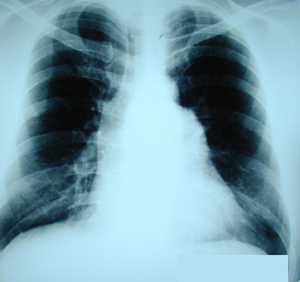

Εικόνα 1

Οπισθιοπροσθία ακτινογραφία θώρακος. Διακρίνεται διεύρυνση του μεσοθωρακίου που οφείλεται στην ύπαρξη όγκου στο μεσοθωράκιο.